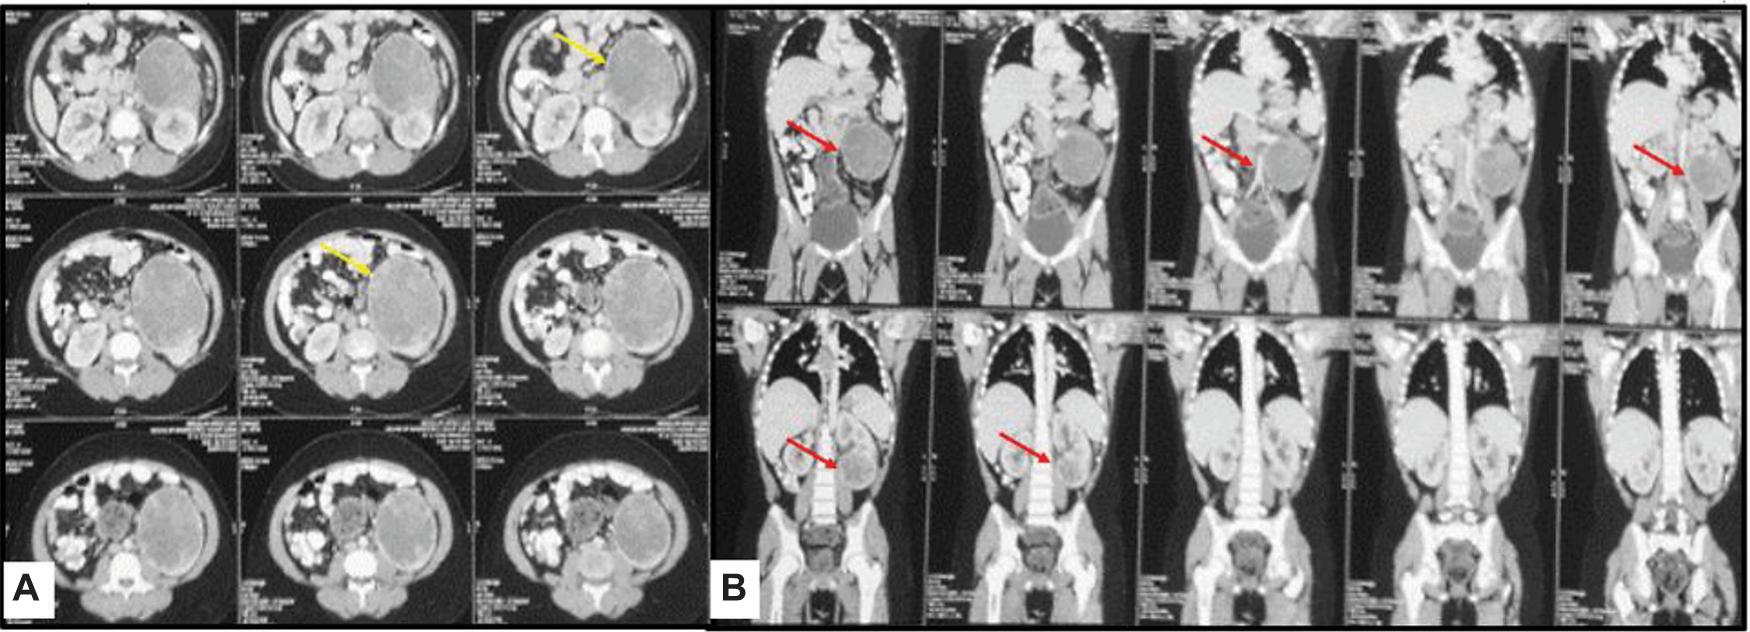

An abdominal ultrasound revealed multiple well-defined elongated echogenic focal lesions close to the cortex in the right and left kidney, suggesting multiple angiomyolipomas, largest being 1.4 × 1.2 cm in size and a separate mass arising from the lower pole of the left kidney (Figure 2). A contrast-enhanced computed tomography (CECT) of the chest and abdomen was performed, which revealed bilateral, multiple, small, non-calcified, and enhancing cortical lesions containing fat that was suggestive of renal angiomyolipomas. Alongside, a 11 × 10 × 9 cm heterogeneously enhancing exophytic solid mass was seen arising from the lower pole of the left kidney causing mild left ureteric compression and mild hydroureteronephrosis (Figure 3). The mass had no fat component. A provisional diagnosis of left RCC was kept, with the rare possibility of epithelioid angiomyolipoma due to the rarity of this tumor.

Figure 3: Images of (A) axial and (B) coronal CECT of the abdomen reveal exophytic heterogeneously enhancing solid mass (arrow) arising from the left kidney. The mass has no fat component in it.